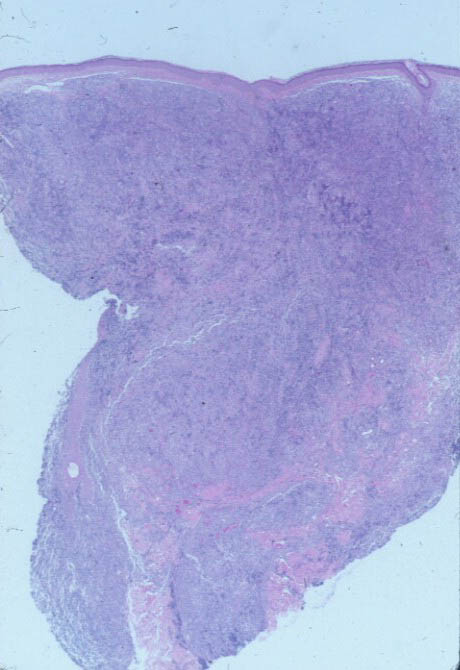

Atlas of skin histopathology

Purple nodule = عقيدة ارجوانية